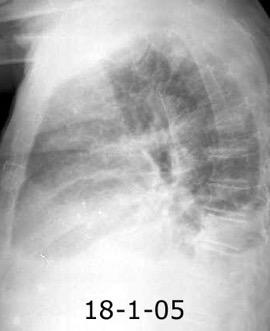

Síndrome de afectación postcardiaca (postcardiac injury)

Post infarto 1-7 % (Dressler)

Trauma cerrado Implantación marcapasos

Cirugía cardiaca. 17-31% (Post.pericardiotomía)

3707 pacientes 29 Derrames (0,78%) > de 25% del hemitórax

Todas menos 2 Izdos.

Angioplastia

By-pass coronario 21-10-03